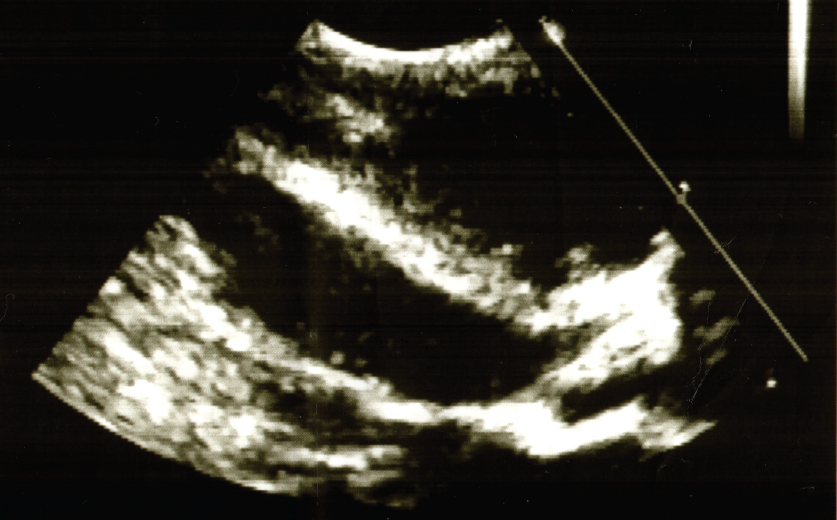

Meckel diverticulum

01/08/2016

Rhonda Graham, DO

A ten-month-old male presented with one large episode of bright-red bloody stool.